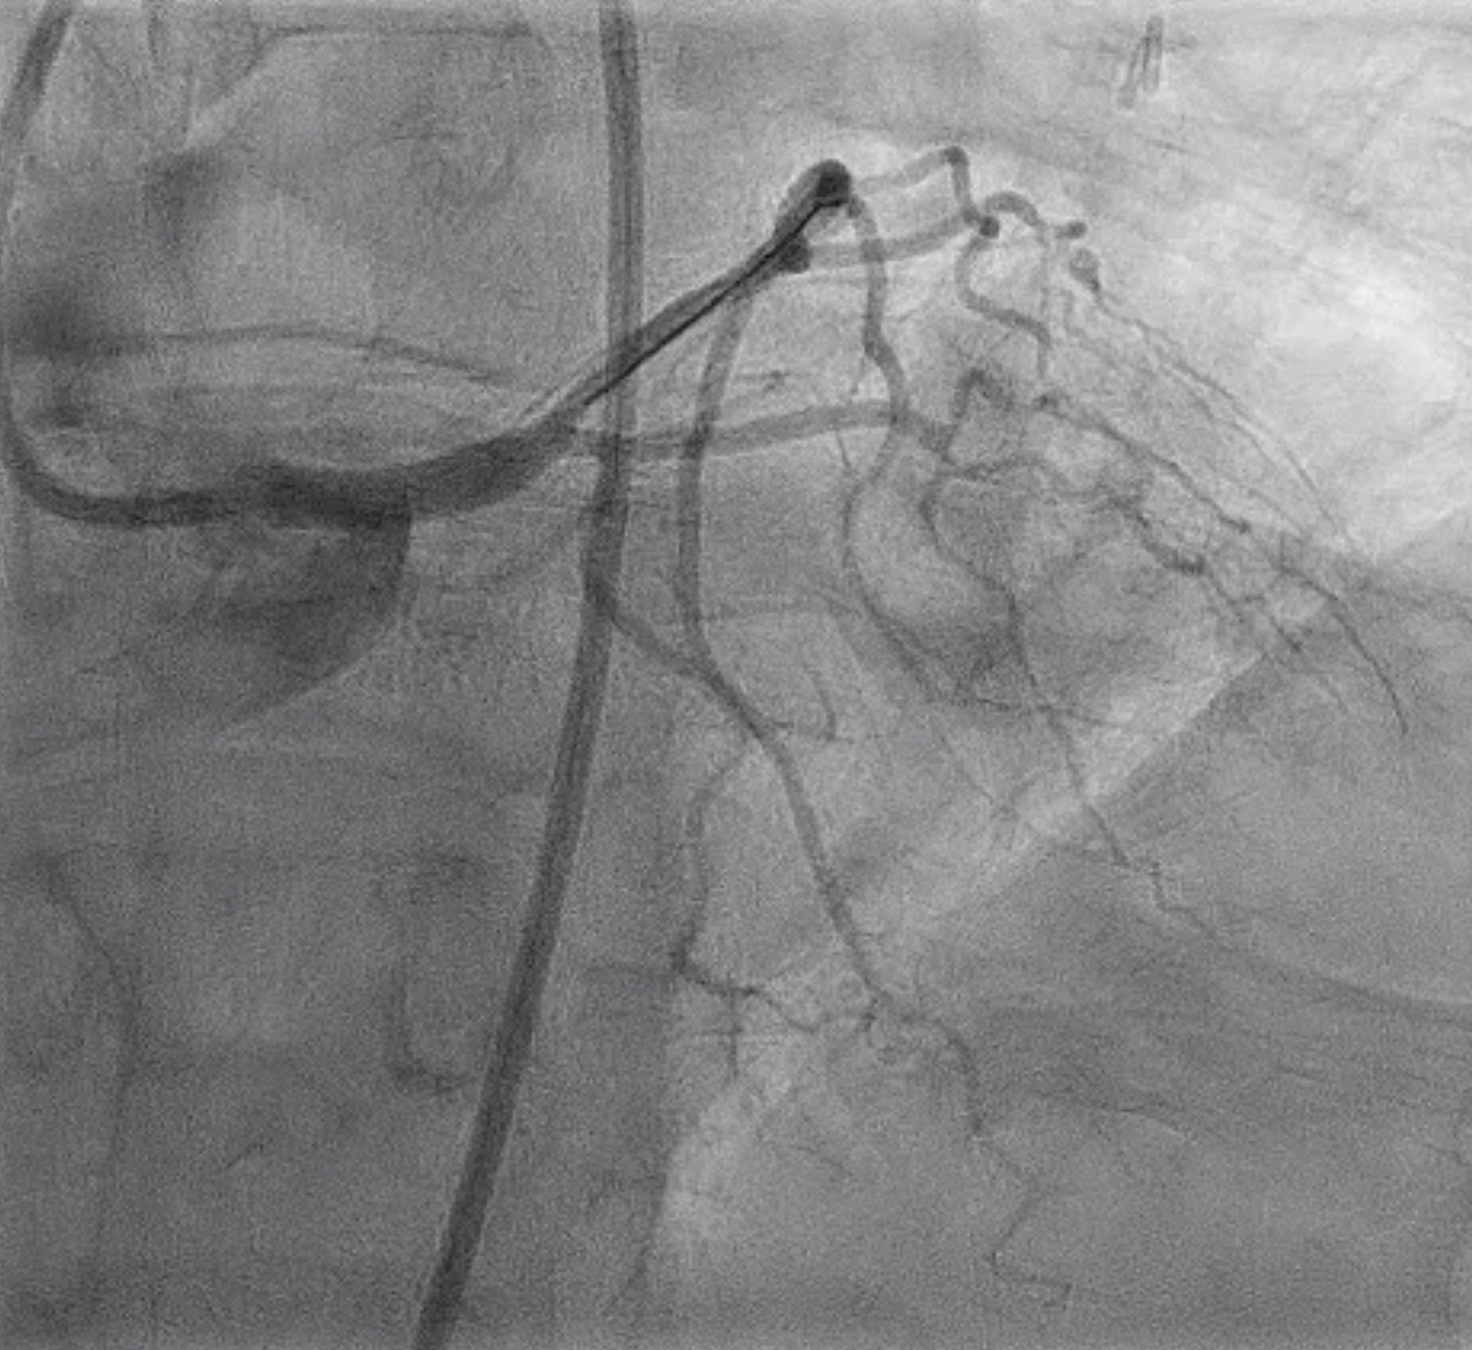

Left main has ostial to mid lesion with 90-95% stenosis. Left anterior descending and left circumflex and right coronary arteries have luminal irregularities without angiographic evidence of obstructive disease. Extreme angles were avoided during diagnostic angiogram in setting of her active pregnancy.

Diagnostic Angiogram LAO20CRA15.mp4

Diagnostic Angiogram LAO21.mp4

Diagnostic Angiogram RAO20CRA20.mp4